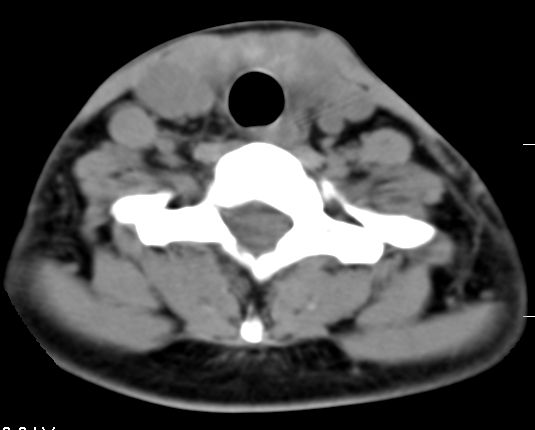

标题: CT9717:F、30Y、颈部左侧包块半年,压痛.患者拒绝作增强。 [打印本页]

标题: CT9717:F、30Y、颈部左侧包块半年,压痛.患者拒绝作增强。

请各位老师帮忙看看左侧甲状腺病灶!

甲状腺弥漫增大,以左叶明显,内见不均匀低密度影,边缘模糊欠清,周围脂肪间隙模糊。

结合病史:考虑亚急性甲状腺炎可能性大。(不知道病人有没有检测tsh t3 t4)

左侧甲状腺及甲状腺狭部弥漫性增大,边缘模糊,未见明确界线.考虑甲状腺炎可能性大.

左侧甲状腺弥满性增大,其内密度均匀减低,气管无受压。周围结构清晰。考虑甲状腺炎可能性大。

甲状腺弥漫性增大病变有以下几种.

1,结节性甲肿;起病慢,无压痛.t3\\t4升高或正常,一般双侧肿大,密度较高.部分可囊变钙化,增强后结节状轮廓显示清楚.轻度强化.

2,亚急性甲状腺炎.临床多见,发病年龄较轻,由上呼吸道感染或病毒性腮腺炎后发病.临床触痛明显.然局部皮肤无红热.t3t4早期升高,后期降低.病灶可单侧或双侧.易炎性渗出,使脂肪密度增高.

3,桥本甲炎(慢性淋巴细胞性甲炎);自身免疫有关.t3t4降低.中老年女性多见.甲状腺弥漫增大,基本对称.,峡部最明显.边界较清.

4,甲状腺癌;一般单侧,进展快.局限性肿块,边界不清,坏死囊变,可伴颈部淋巴转移.包膜侵犯.增强明显不均质强化.